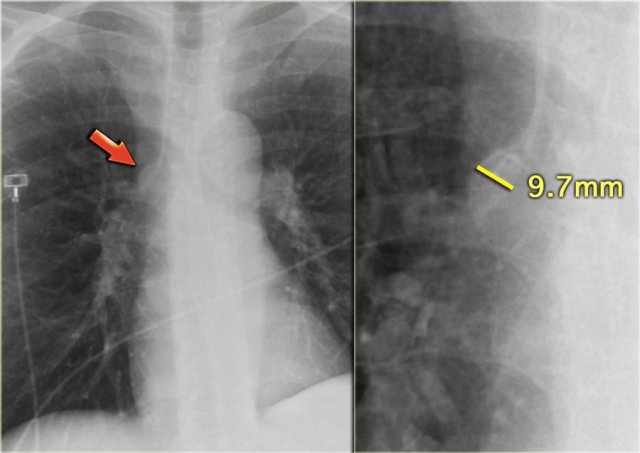

Pleural effusion more evident on lateral view Pleural effusion more evident on lateral view

Pleural effusion is bilateral in 70% of cases of CHF.

When unilateral, it is slightly more often on the right side than on the left side.

There has to be at least 175 ml of pleural fluid, before it will be visible on a PA image as a meniscus in the costophrenic angle.

On a lateral image effusion of > 75 ml can be visible.

If pleural effusion is seen on a supine chest film, it means that there is at least 500 ml present.

On the left images of a patient who has bilateral pleural effusions.

Notice that it is more evident on the lateral view.